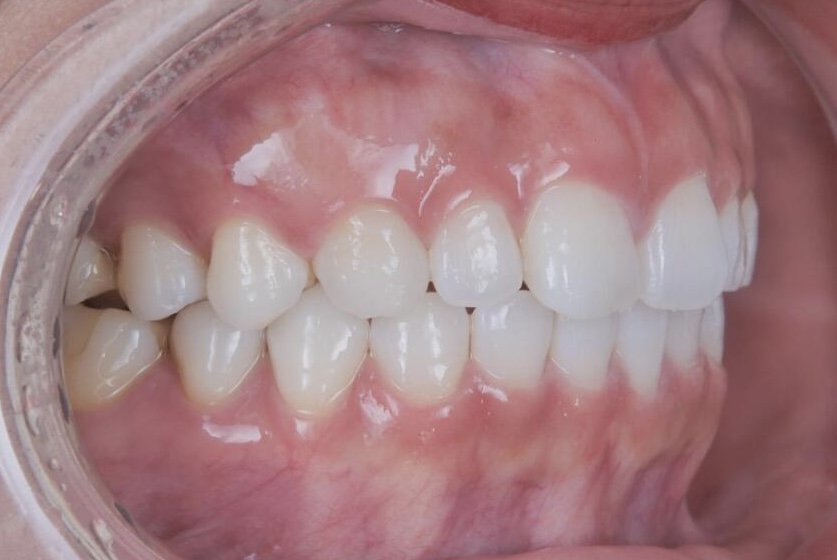

BEFORE

20代女性の患者さまで、4人のお子さまを育てながら、できるだけ目立たない方法ですきっ歯を治したいとご相談に来院されました。子育てや日常生活への影響をできる限り抑えながら治療を進めたいというご希望を踏まえ、当院で専門的に行っているマウスピース矯正にて治療を進めました。

| 主訴 | すきっ歯が気になる |

| 施術内容 | 歯全体のマウスピース矯正システム「インビザラインライト」を用いた治療 |

| 治療期間 | 1年 |

| 費用 | 528,000円 |